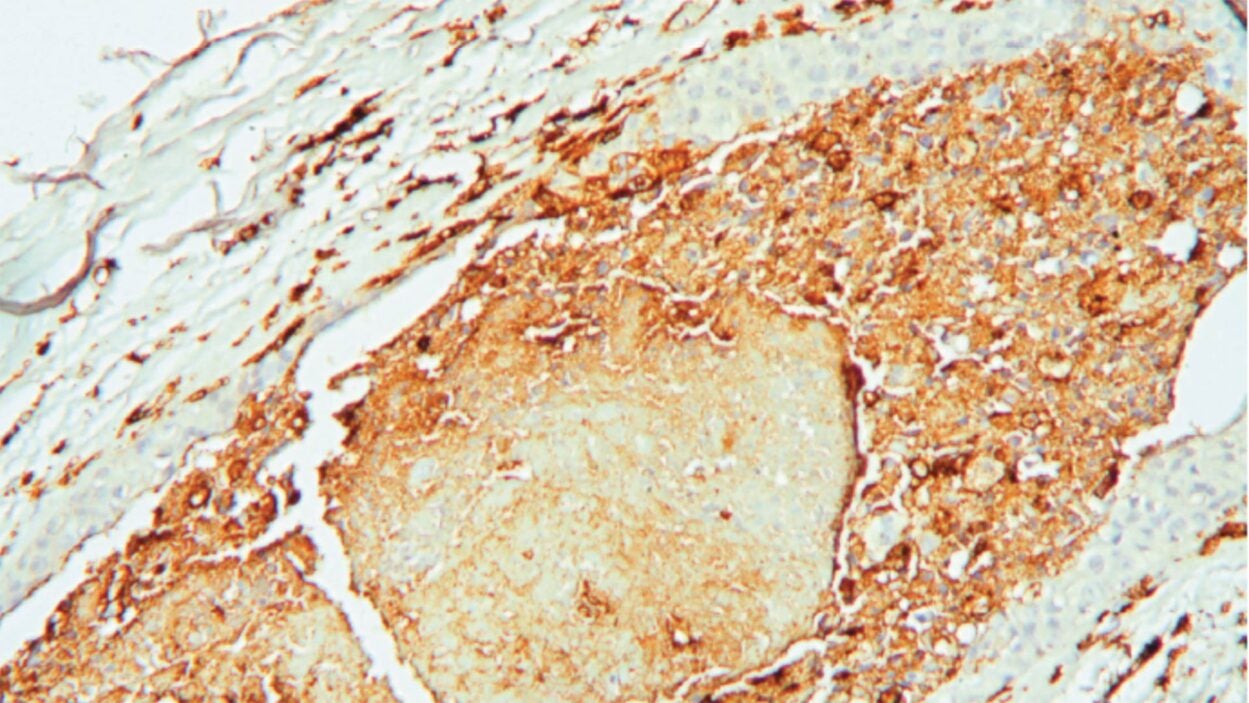

CSHL researchers examined tissue samples from a 59-year-old woman diagnosed with stage 1 triple-negative breast cancer. Read the story »

A tumor is not just a tumor. It’s a complex ecosystem scientists unpacked at the CSHL meeting, Biology of Cancer: Microenvironment & Metastasis. Read the story »

An angry peacock is no joke. Like the colorful bird and its tall tail feathers, cancer biology can make for some eye-catching images. Read the story »